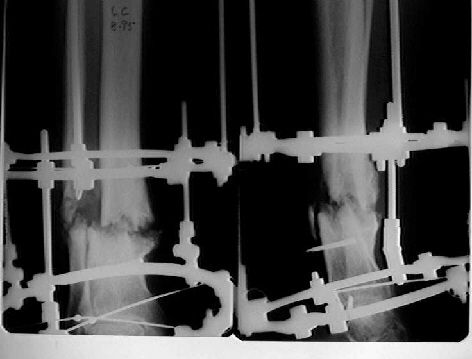

Female. 65 years old. 2 years ago trimalleolar fracture left ankle. First ORIF failed. Second ORIF with autologous graft at the fibular fracture was complicated by infection. The X-ray pictures show the actual situation. What are the suggestions of the group?

It seem a stiff pseudarthrosis. I will do a axial correction and lengthening if necessary with Ilizarov frame without any corticotomy. Probability of success will be 100% and relapse of infection 0%. You can see one case attached.

Best regards,

Nuno Craveiro Lopes

Almada - PORTUGAL